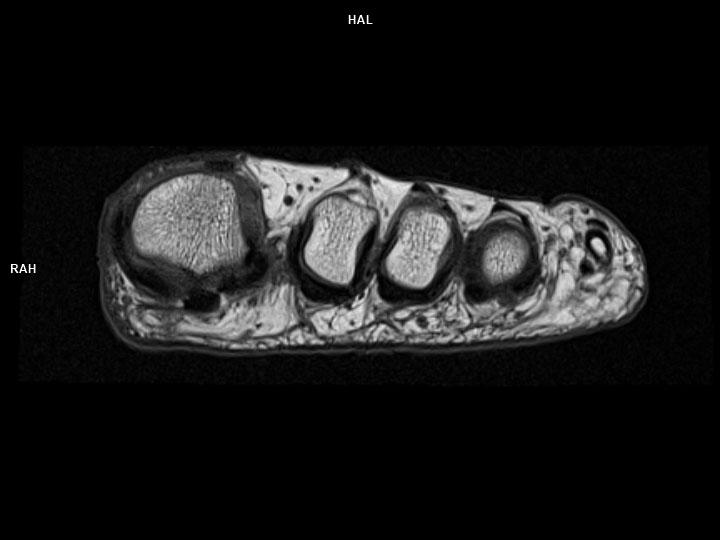

Axial T1 TSE-MAGNETOM Lumina

Axial T1 TSE-MAGNETOM Lumina/Coil-Foot Ankle 16/Resolution-432/Scan Time-1:49